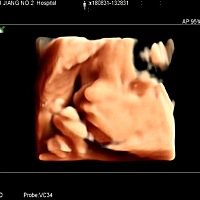

孕35周了,有没有懂的宝妈帮看下男孩女孩😝😝